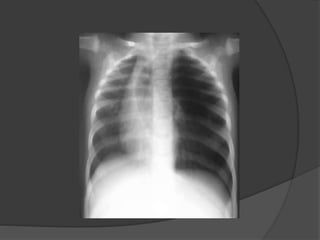

Imagerie: Radiographie du thorax

Opacité hétérogène

para-hilaire droite:

KB